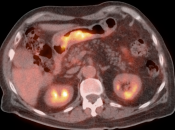

• The utility of PET/CT lies in its assessment of regional nodes and distant metastatic disease.

• Distant Disease: Most commonly to the liver, peritoneum, lung and bone.